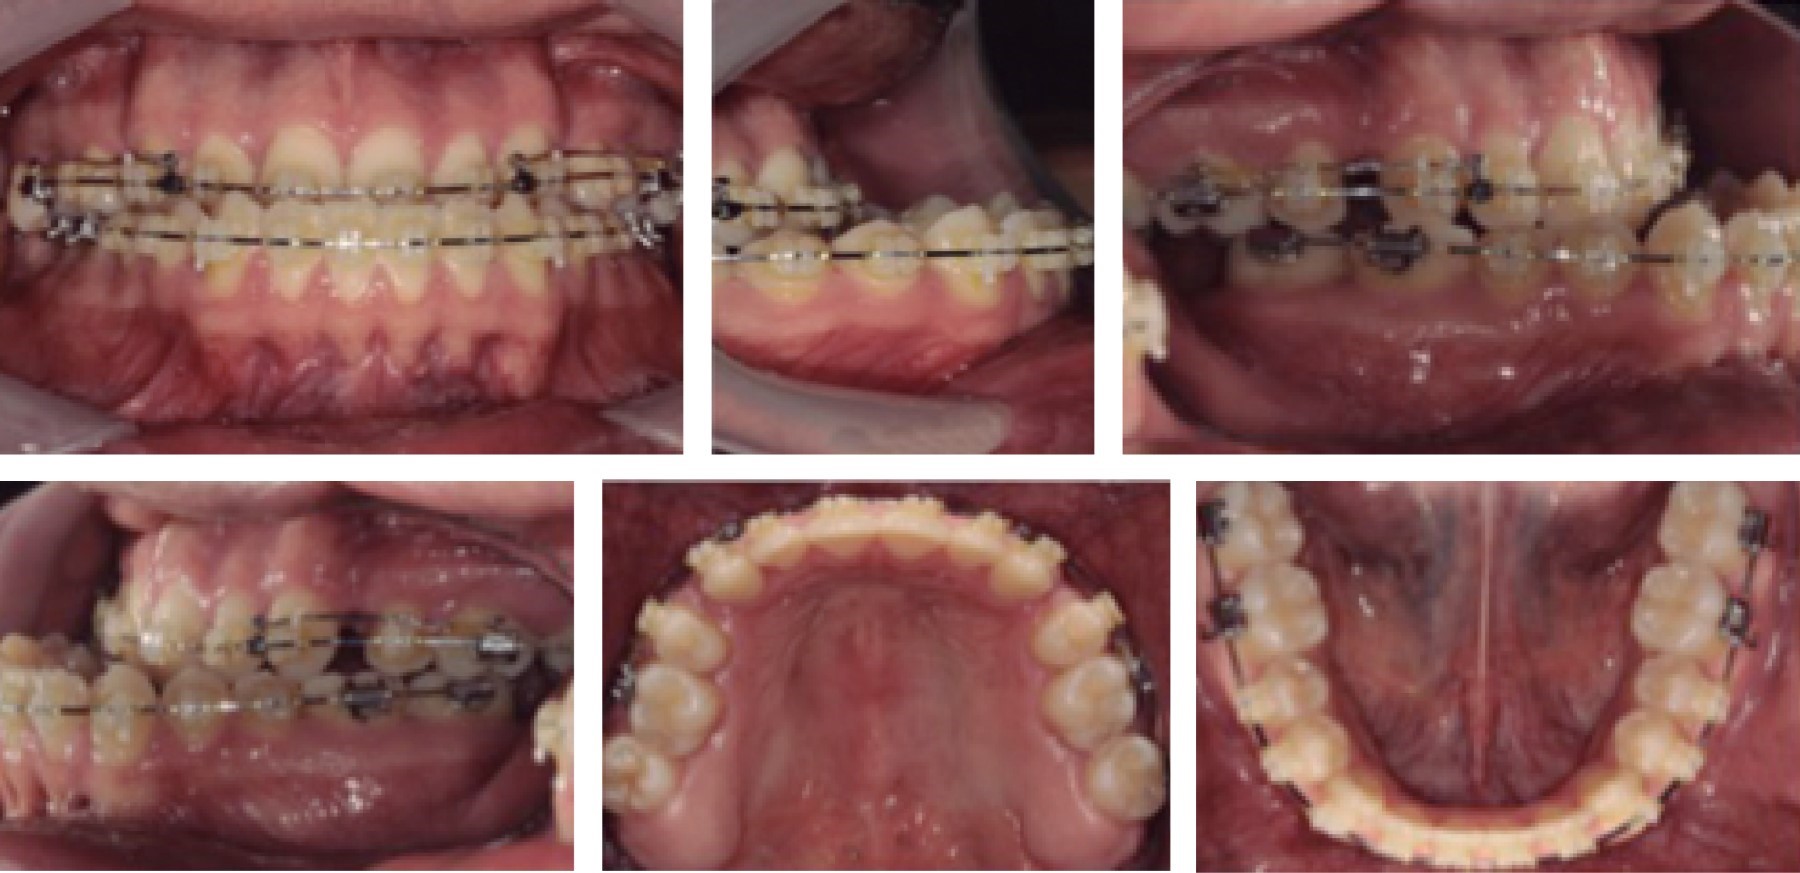

En el postquirúrgico, el paciente evidencia el cambio (Figuras 5 y 6), con un ángulo frontonasal de 130o, nasolabial de 99o y mentolabial de 120o, un overjet positivo de 2 mm, oclusión clase I canina de Angle y clase II molar funcional de Angle.

En la actualidad, el paciente se encuentra en tratamiento ortodóncico postoperatorio en fase de cierre de espacios para después continuar con la fase de asentamiento y detallado (Figuras 7, 8, 9, 10, 11, 12, 13 y 14).

Figura 5

Figura 6

Figura 7

Figura 8

Figura 9

Figura 10

Figura 11

Figura 12

Figura 13

Figura 14